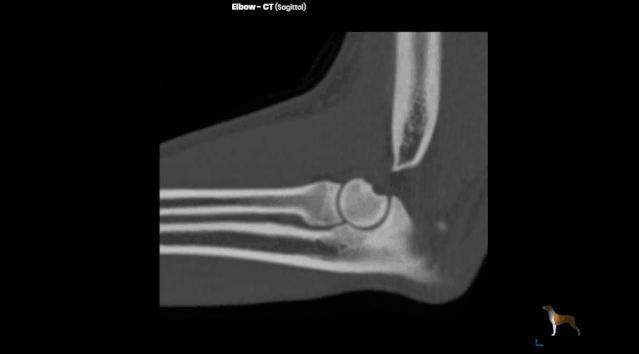

CT也是一种 X 线检查,它能对骨折部位进行多层的扫描,提供每一层的截面图像,使骨折的图像呈现避免了其他组织的干扰,更清楚地显示出来。在普通的X线片上显示不出来骨折都能在CT片上清楚地显示。

术前x-ray显示,六一的骨折为 左前肢肱骨中远段骨折 ,骨折类型为横骨折。

六一小朋友的年龄仅有3个月,体重仅1kg,对于这样的幼猫,陈旧性骨折发生二次骨折的内固定手术无疑是一个严峻的挑战。六一的主治医生张海峰院长使用接骨板板对六一进行了骨折的内固定。